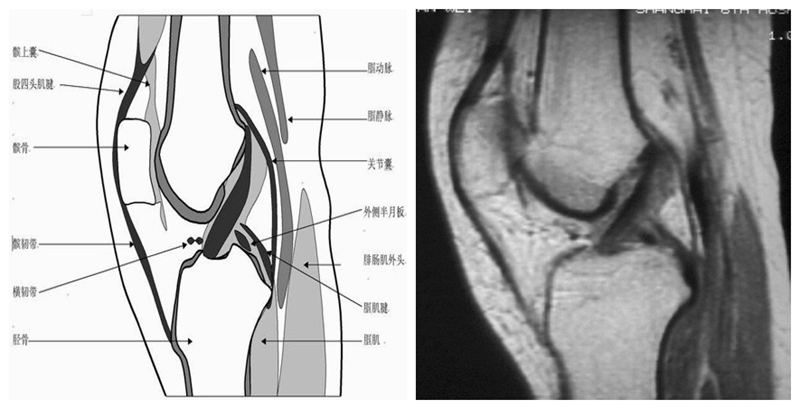

膝关节冠状面MRI解剖

显示内外侧副韧带、腘肌和拱状韧带,有无信号和结构改变,侧重关节胫股软骨的两边和半月板的体部。

冠状位解剖第三层

冠状位解剖第四层